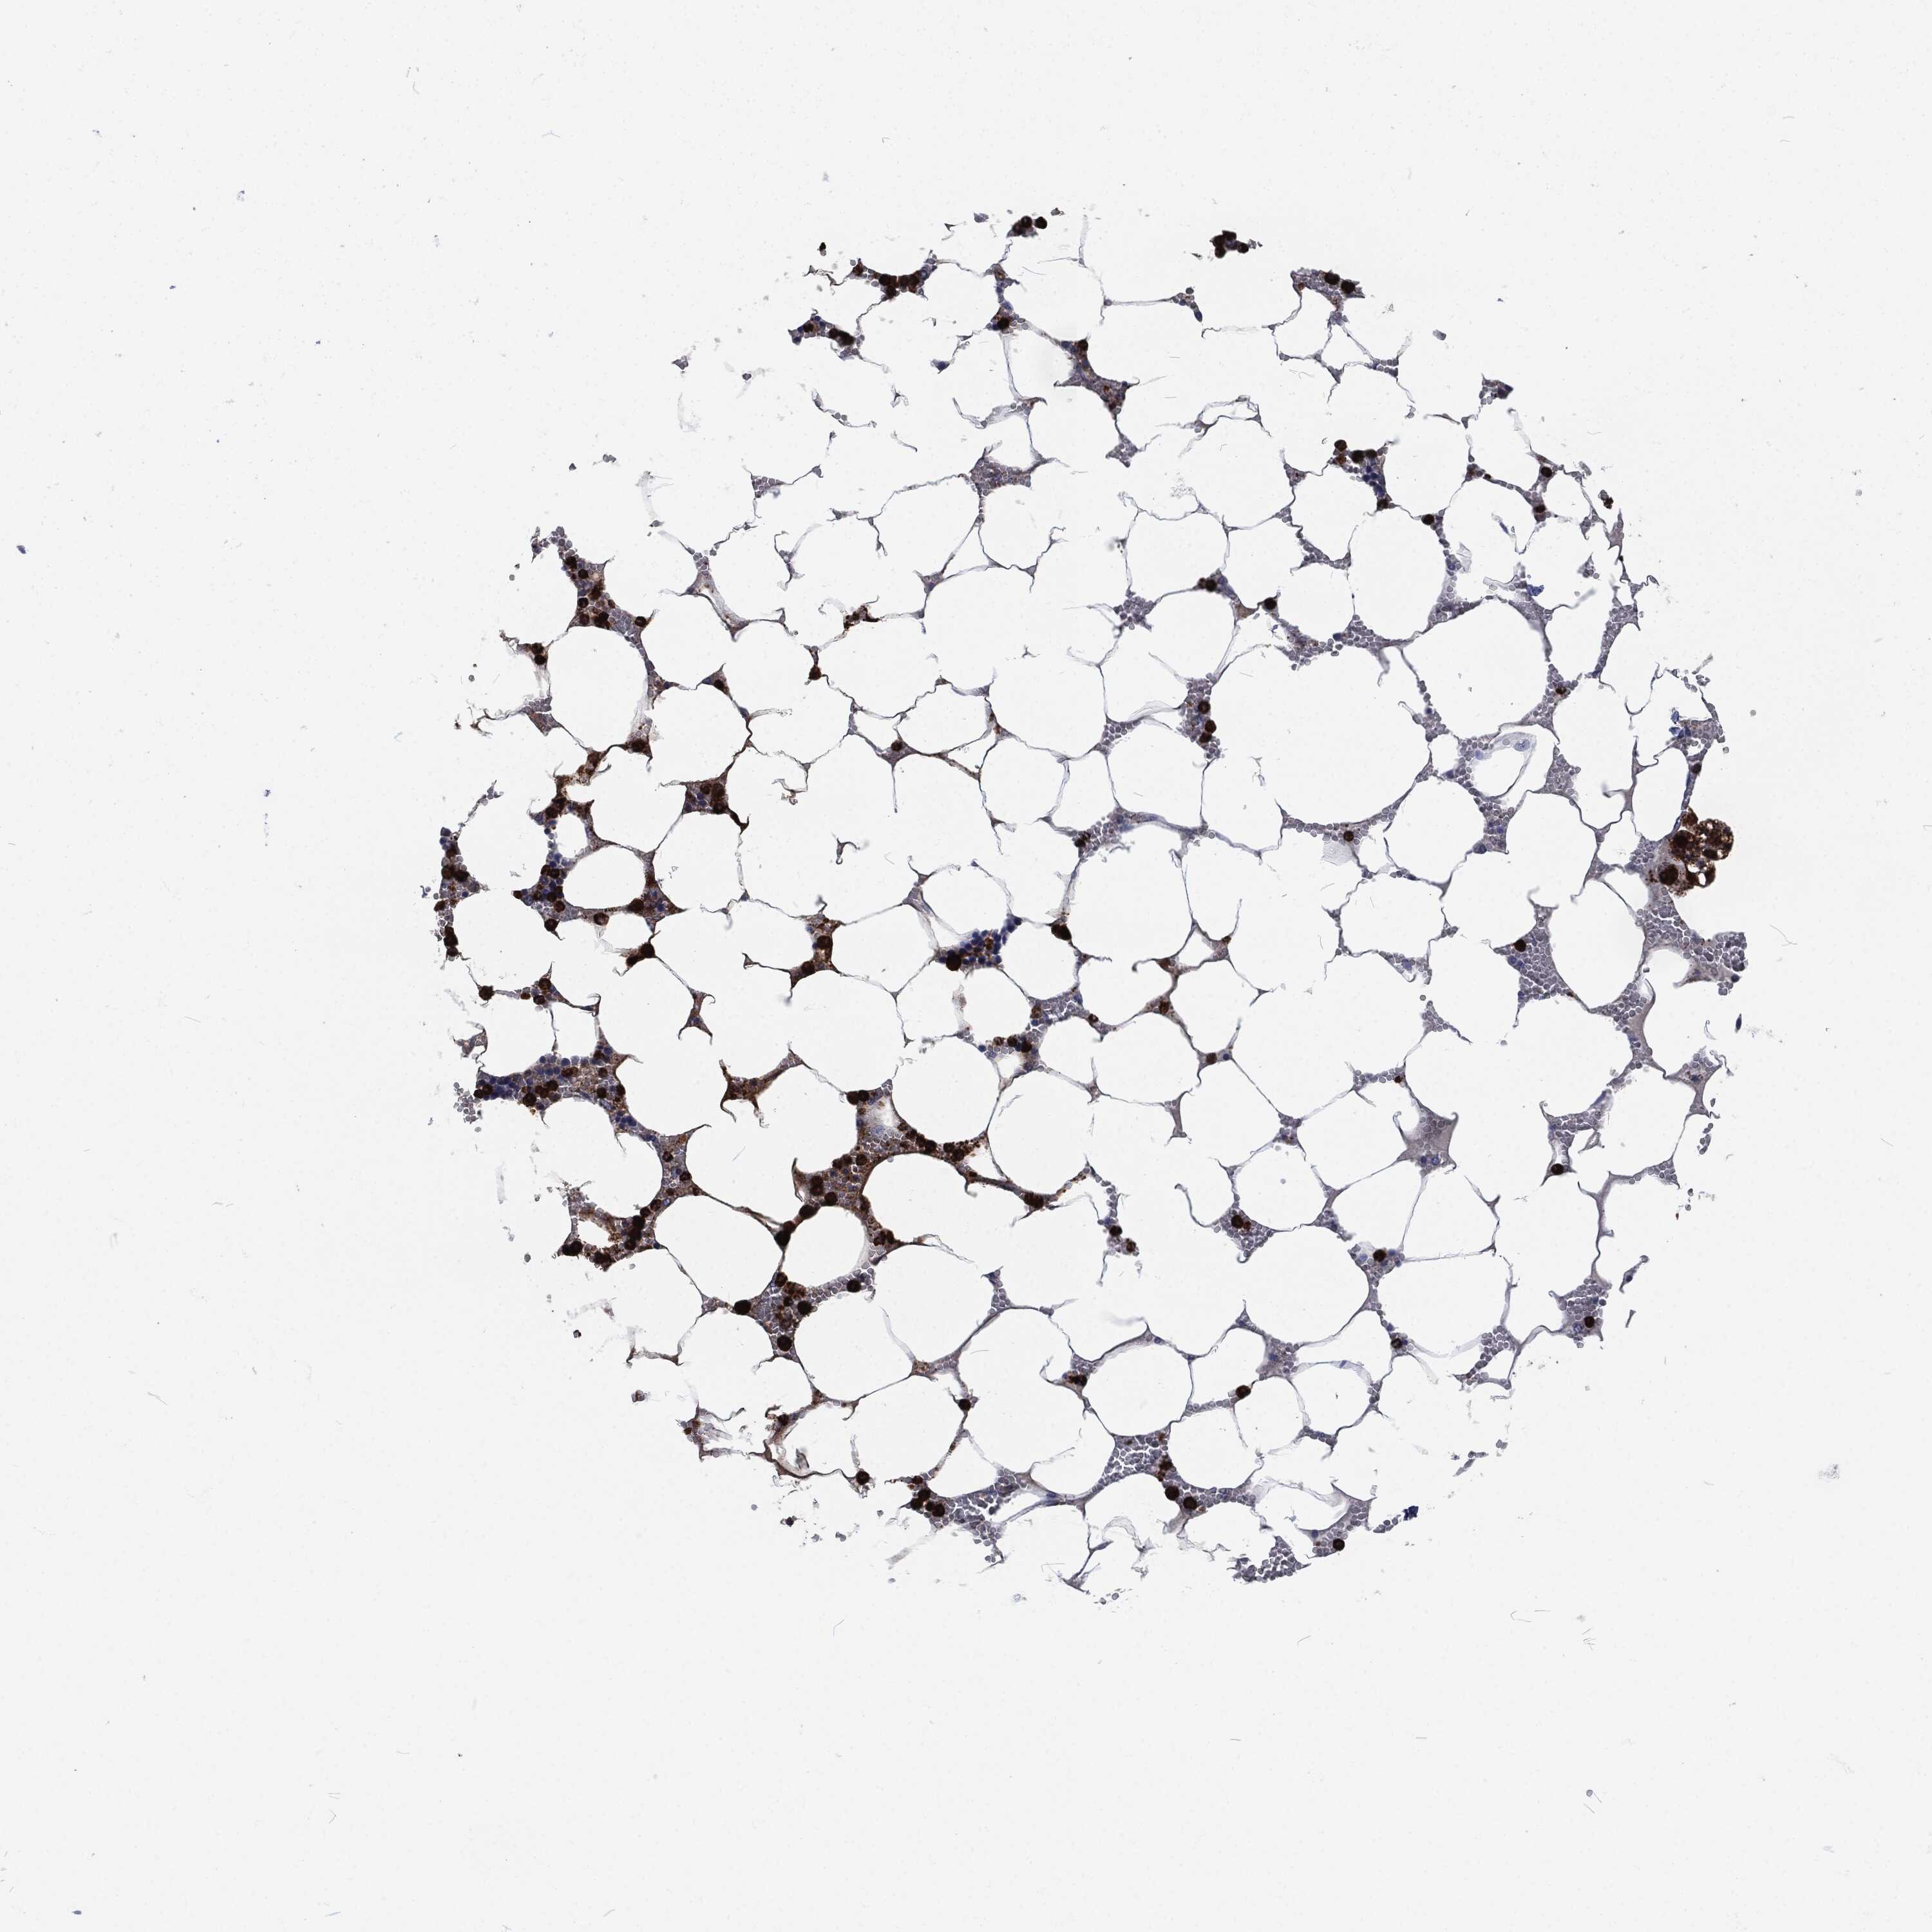

BONE MARROW - Antibody stainingi

Antibody staining in the annotated cell types in the current human tissue is reported as not detected, low, medium, or high, based on conventional immunohistochemistry profiling in selected tissues. This score is based on the combination of the staining intensity and fraction of stained cells.

Each image is clickable and will lead to virtual microscopy that enables deeper exploration of all samples and also displays staining intensity scores, fraction scores and subcellular localization as well as patient and tissue information for each sample.

Antibody HPA021147Antibody HPA061464Antibody CAB000059Antibody CAB080352Antibody CAB080353Antibody CAB080354

Hematopoietic cells LowHighMediumHighHighHigh